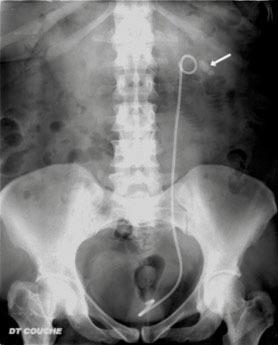

ASP couché de face montrant un calcul rénal et une sonde double J. Attention car 10 % des calculs sont radio-transparents, les calculs millimétriques peuvent également ne pas être mis en évidence par un ASP et des calculs peuvent être masqués par la trame osseuse ou l'aéroiléie. Inversement, des éléments non lithiasiques calcifiés se projetant sur les voies urinaires peuvent simuler une lithiase.